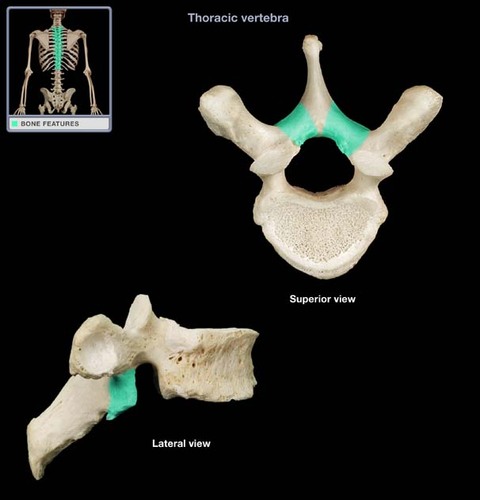

Thoracic Vertebrae

vertebral arch

lamina